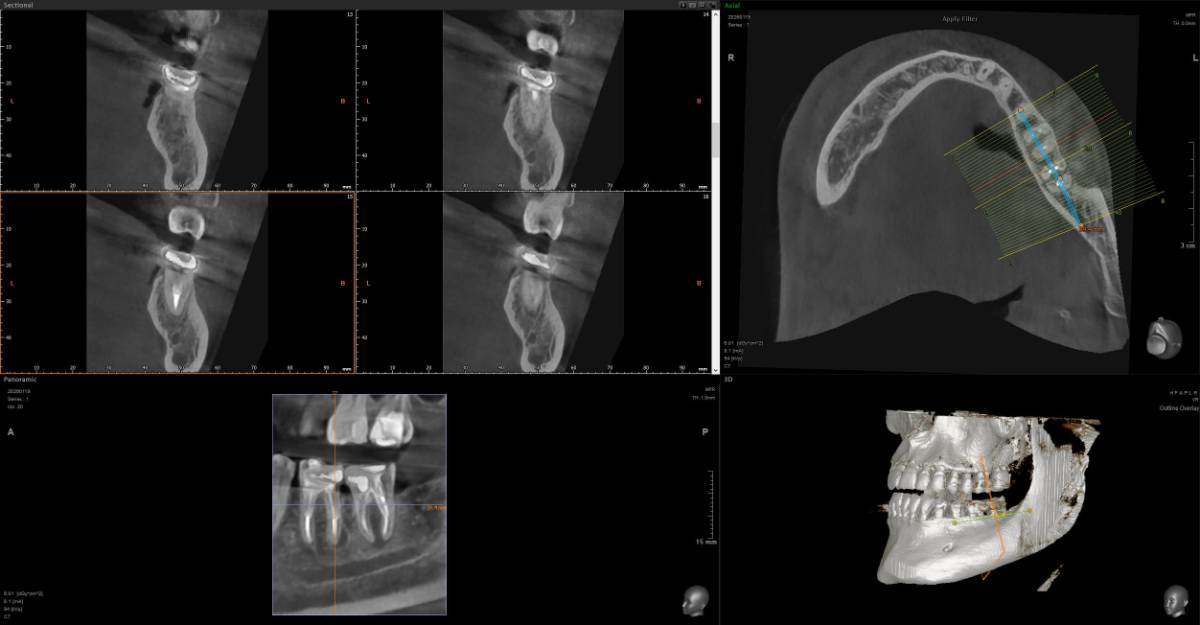

A-V-S Опубликовано 3 марта Поделиться Опубликовано 3 марта Здравствуйте. У меня такая ситуация: В начале января 2026 начал болеть зуб 7ка снизу слева - боль развивалась постепенно - в итоге стало больно жевать. Сделал КТ. Лечащий стоматолог сказал, что это проснулось спящее воспаление, перелечивать каналы зуба сложно - надо сверлить буром и доставать стекловолоконный штифт - надо удалять. В следующие дни открылся свищ и боль ушла. Свищ продолжает быть с периодическим набуханием и сдуванием после выброса гноя белого цвета. Этот зуб лечили с установкой стекловолоконного штифта чуть больше 5 лет назад. Посмотрите, пожалуйста, приложенные снимки и посоветуйте как быть - можно ли перелечить и сохранить зуб ? Ссылка на комментарий

АнтонТЛТ Опубликовано 3 марта Поделиться Опубликовано 3 марта Добрый вечер, лучше выложить несколько срезов этого зуба, либо архив с кт. По представленным снимкам, есть подозрение о наличии трещины между корнями зуба. 1 1 Ссылка на комментарий

red_butler Опубликовано 4 марта Поделиться Опубликовано 4 марта Здравствуйте, Вы выложили не срезы. а реконструкцию. Залейте кт в облако и скиньте сюда ссылка на скачивание Ссылка на комментарий

Гарриевич Опубликовано 6 марта Поделиться Опубликовано 6 марта Не знаю обрадует Вас это или огорчит, но зуб можно сохранить соседний тоже с воспалением кстати 1 1 Ссылка на комментарий

red_butler Опубликовано 9 марта Поделиться Опубликовано 9 марта В 03.03.2026 в 22:49, A-V-S сказал: можно ли перелечить и сохранить зуб ? можно Ссылка на комментарий